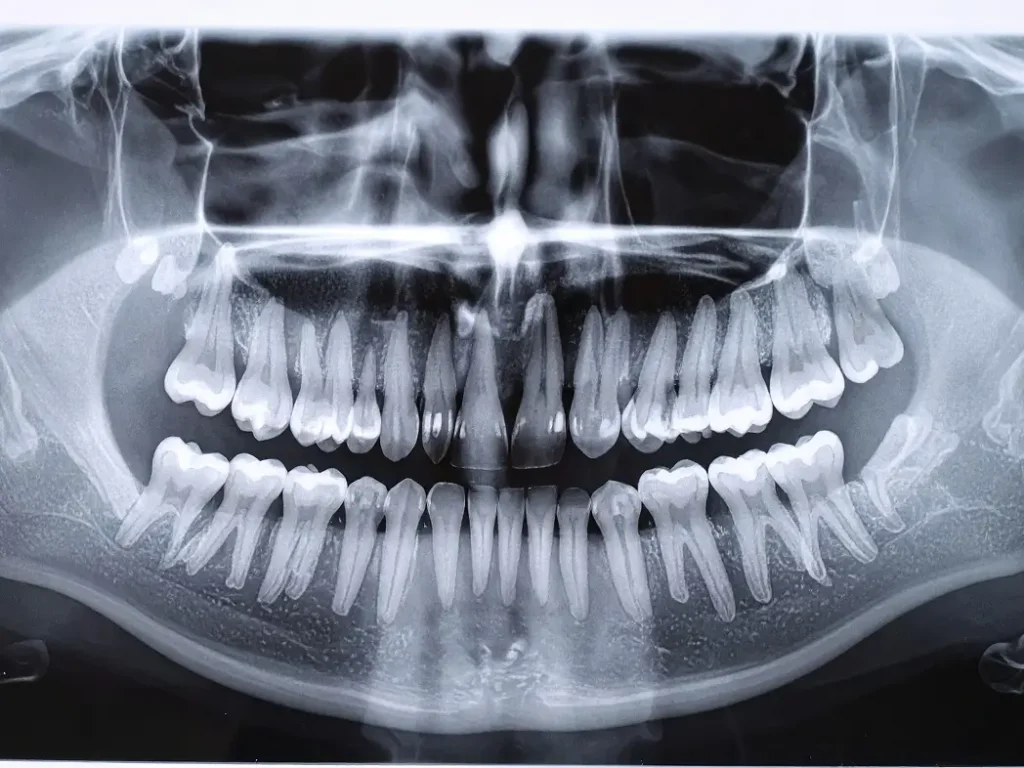

検査5 レントゲン検査(⁨⁩重度の場合)

歯周病の検査でレントゲン写真は必須です。軽度の歯肉炎を除き、通常の基本検査、及び歯周精密検査では、口腔内全体の写真(パノラマ写真)を撮ります。

また必要に応じて歯科用3Dレントゲン写真を撮る場合もあります。

3Dレントゲンにより歯の周囲の骨を見るだけでなく親知らず、虫歯の状況、かぶせ物の適合、歯の根の状態などさまざまな視点から総合的に診断することができます。